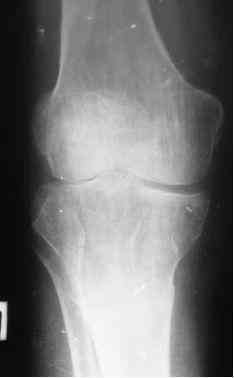

Анамнез: в 1992 г. оперирован в РНЦ «ВТО» по поводу ложного сустава шейки правого бедра (Р-снимок в приложении), 1994 перенес инсульт с исходом в правосторонний гемипарез. Передвигался без костылей, имея укорочение этой конечности на 3,5 см, порочную сгибательно-приводящую установку правого бедра и ДОА правого коленного сустава III ст. с перегрузкой латерального компартмента. Имеются дегенеративно-дистрофические изменения в поясничном отделе позвоночника. Больной до последнего времени «таксовал» на своей машине. 23 дня назад, поскользнувшись, упал в своей квартире, получил 2-х лодыжечном переломе костей правой голени с подвывихом стопы кнаружи (Р-граммы правового коленного и г/стопного суставов прилагаются). Помощь оказана в городском травмпункте г.Темиртау (Казахстан) Лечился гипсовой шиной, как рассказывает больной манипуляций на г/стопном суставе не проводили, посчитали, что все в порядке. Мое мнение - для создания опорной конечности необходимо произвести первичный артродез.Попов Виктор, г.Караганда.